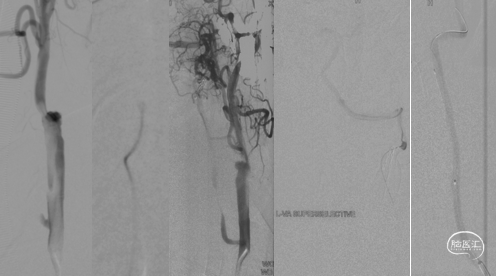

CTA和DSA

左右滑动查看更多

CTA和DSA所见:双侧颈内动脉闭塞,右侧椎动脉发出PICA后闭塞,左侧椎动脉V1-V2段闭塞。两条健壮的侧枝通过肌支吻合汇入左椎动脉V2段,构成了整个大脑大部分供血的主要来源。双侧颈外动脉亦有少量血流供应颅内。这样的颅内供血很容易发生失代偿,导致TIA甚至脑梗。